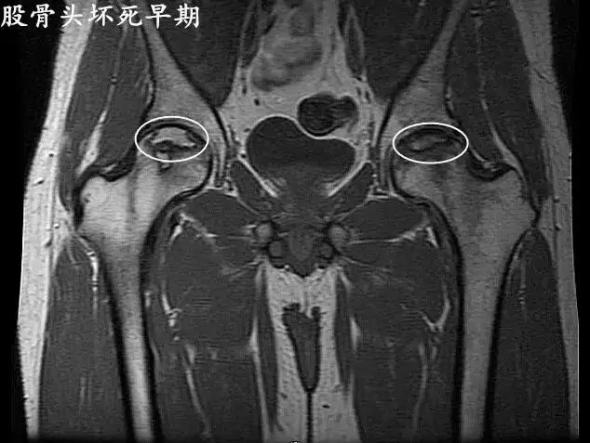

股骨頭壞死早期信號有哪些?北京公立三甲醫院骨傷科主任醫師王春。股骨頭壞死發病的早期信號有哪些?股骨頭壞死可以有很長的潛伏期,在發病以后早期的癥狀一般不明顯,非常容易被患者忽視。提示大家如果有以下癥狀就要提高警惕。

股骨頭壞死最初的癥狀就是疼痛,它可以出現在腹股溝或者臀部的疼痛,還可以出現膝關節附近的疼痛,下肢怕涼無力。這種癥狀往往在熬夜以后加重,休息后可以緩解。當然少數患者早期也可以出現持續性疼痛,這樣一般來講就比較容易發現。

還有一部分患者早期就可以出現髖關節的活動受限。如果您出現了上述的癥狀就要及時的到醫院進行檢查,通過x光片核磁共振就可以排除早期的股骨頭壞死。由于股骨頭壞死的早期癥狀體征不明顯,容易發生誤診漏治的情況。

如果您是股骨頭壞死的高危人群,比如長期的飲酒長期的食用糖皮質激素治療相關的疾病,還有髖部的外傷病史,建議您多了解一些股骨頭壞死的早期癥狀,做到早發現早治療。

股骨頭壞死早期癥狀。股骨頭壞死這幾年發病率有所增高,而且在青壯年當中發病率特別高。早期癥狀主要是髖關節的疼痛,疼痛是在大腿的根部腹股溝的附近。它的疼痛特點最主要就是行走的時候會出現疼痛,但是臥床休息以后疼痛就馬上緩解。

所以大家很容易把這個病給忽視,錯過了最佳的診斷和治療時期。所以我在這里提醒大家,如果您出現了行走時髖關節疼痛,而且在臥床休息后疼痛明顯的減輕。如果這個癥狀持續存在,那么您一定要到醫院就診,做相關的檢查,早期診斷早期治療,可以得到好的預后。